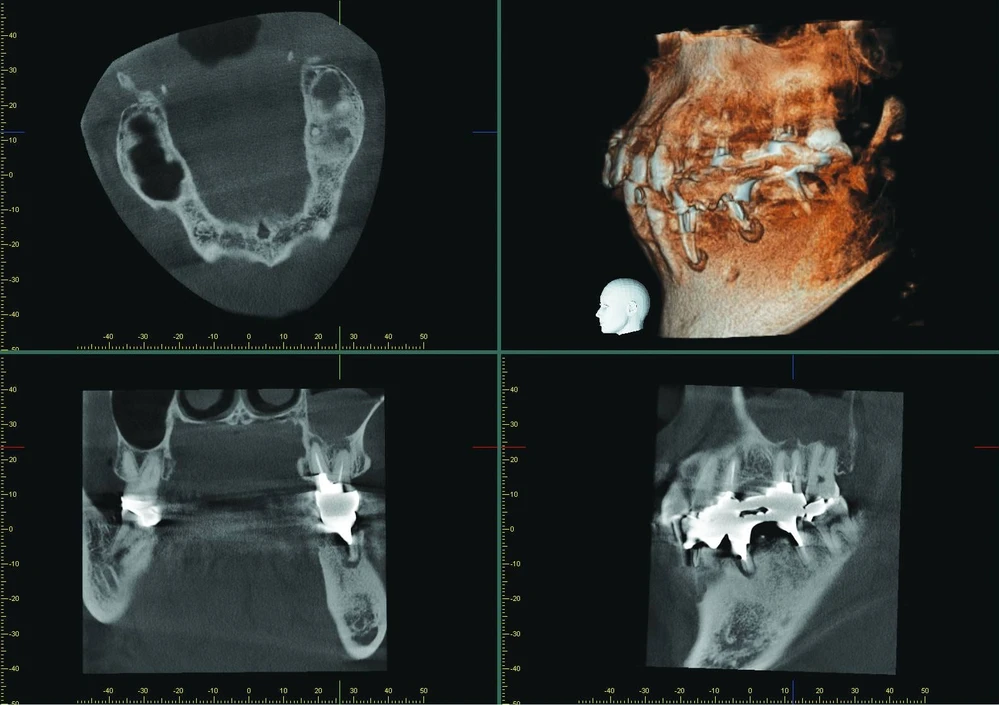

Images taken with Veraviewepocs 3D R100

The patient presented with an unclear situation around tooth 26, which had undergone endodontic treatment before. Conventional 2D X-rays did not allow a conclusive diagnosis; therefore, a 3D scan was performed with Veraviewepocs 3D R100. The sagittal and coronal view showed that the endodontic treatment had not been successful and that there were apical defects on the buccal and palatal root.

The sagittal view clearly confirms perforation of the Schneiderian membrane, and the coronal view revealed an odontogenic maxillary sinusitis and pachymenia. The injury of the sinus membrane may have been overlooked in this case if the diagnosis had been formulated on the basis of an X-ray that did not show the problem so clearly.